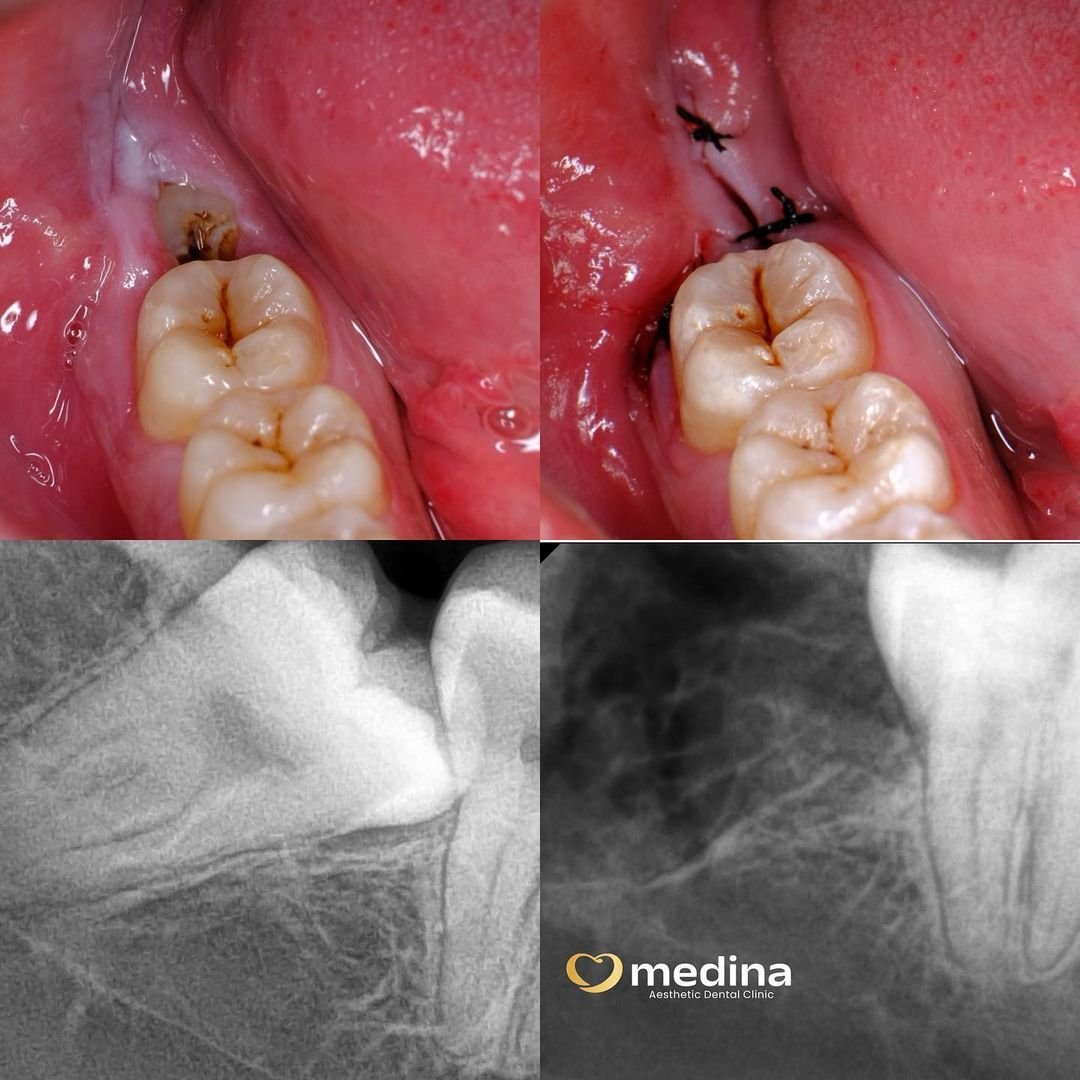

Cabut Gigi Bungsu

adalah pencabutan gigi dengan prosedur bedah mulut tanpa harus opname.